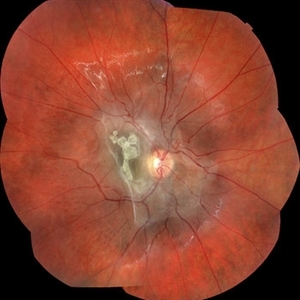

Fundus photograph montage of a 7-year-old boy with an astrocytic hamartoma involving the macula.

Photographer: John Golding BA, Vitreous Retina Macula Specialists of Toronto

Imaging device: Topcon TRC-50 Dx